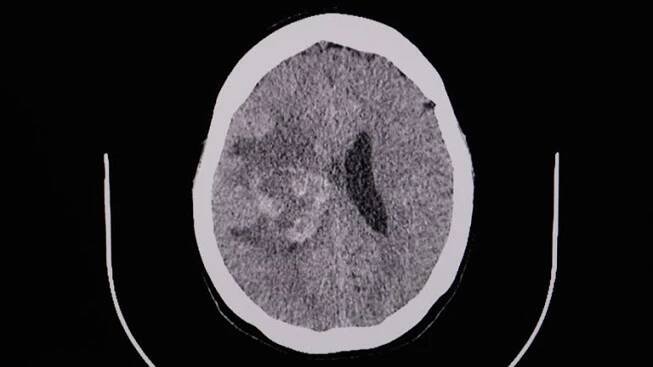

CT sken mozku pacienta po dopravní nehodě s akutním subdurálním hematomem

Michael Schumacher má několik otoků na mozku, jeden se v úterý podařilo lékařům odstranit. Co je subdurální hematom? Druh traumatického poranění mozku, při kterém se přetrhají žilky v ochranné membráně mozku a  dojde k otoku. Krev se hromadí mezi tvrdou plenou mozkovou a povrchem mozku a způsobuje tlak na mozkovou tkáň. Mezi symptomy patří bolest hlavy, zvracení, poruchy vědomí a někdy i zhoršení intelektu.